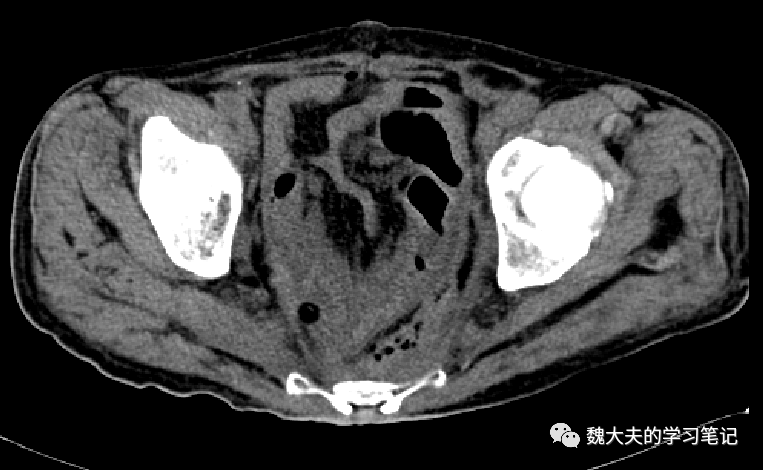

影像学资料:

图片

术后CT平扫